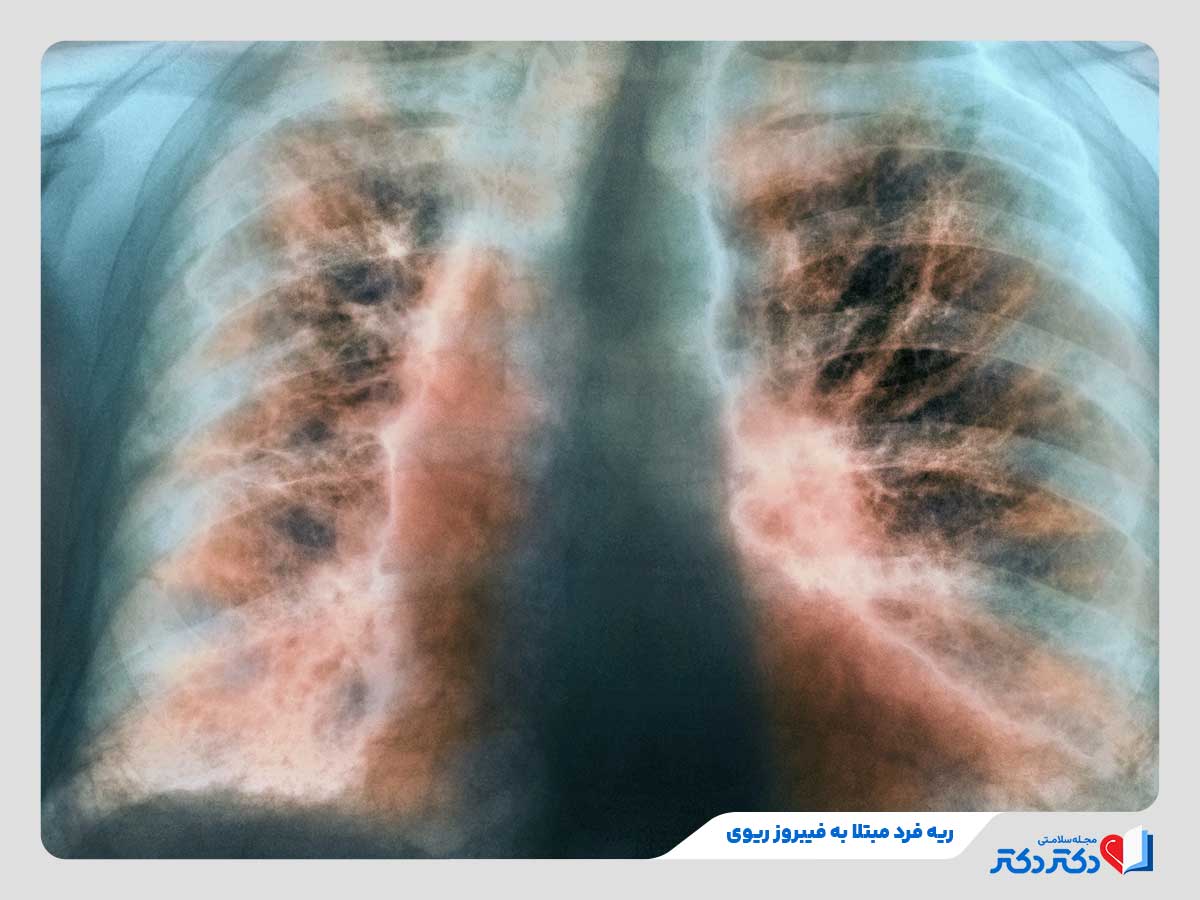

- فیبروز ریوی ایدیوپاتیک (IPF): تشکیل بافت اسکار در ریه که بدون هیچ علت مشخصی رخ میدهد.

بیماریهای فیبروتیک ریه

این بیماری های ریه شامل حالاتی می باشند که در آنها بافت ریه به مرور زمان دچار فیبروز (راه اندازی بافت اسکار) میبشود. این بافت اسکار سفت و غیرقابل انعطاف است و علتکاهش ظرفیت ریه، سختی تنفس و افت انتقال اکسیژن میبشود. بیماران مبتلا به این بیماری زیاد تر حس میکنند که نمی توانند نفس عمیق بکشند. بیماریهای شایع در این دسته شامل موارد زیر خواهد شد:

- فیبروز ریوی ایدیوپاتیک (IPF) از شایعترین نوع فیبروز ریه با علت ناشناخته